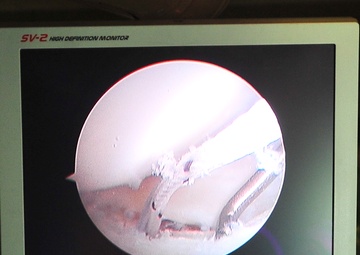

The screen from an arthroscopic camera shows an internal view of a torn labrum being repaired by members of the 51st Medical Group here June 7, 2012. Once the labrum is repaired, it will take approximately 12 weeks for the labrum to re-attach itself to the rim of the bone and for the patient to feel strength in the shoulder. (U.S. Air Force photo/Senior Airman Adam Grant)...